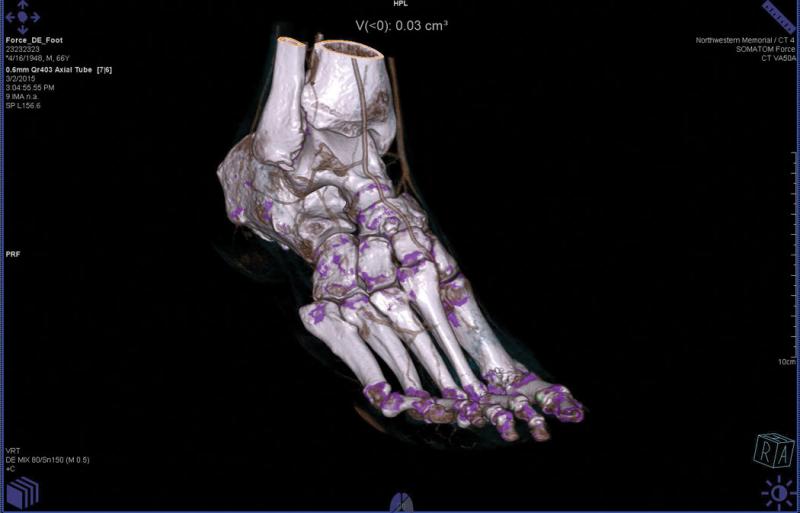

September 9, 2015 — The U.S. Food and Drug Administration (FDA) granted 510(k) for Philips Healthcare’s Spectral ...

When 64-slice computed tomography (CT) systems were introduced nearly a decade ago, they were purchased in large numbers ...

Computed tomography (CT) has enjoyed a place of prominence in medical imaging since its creation in the 1970s. The ...